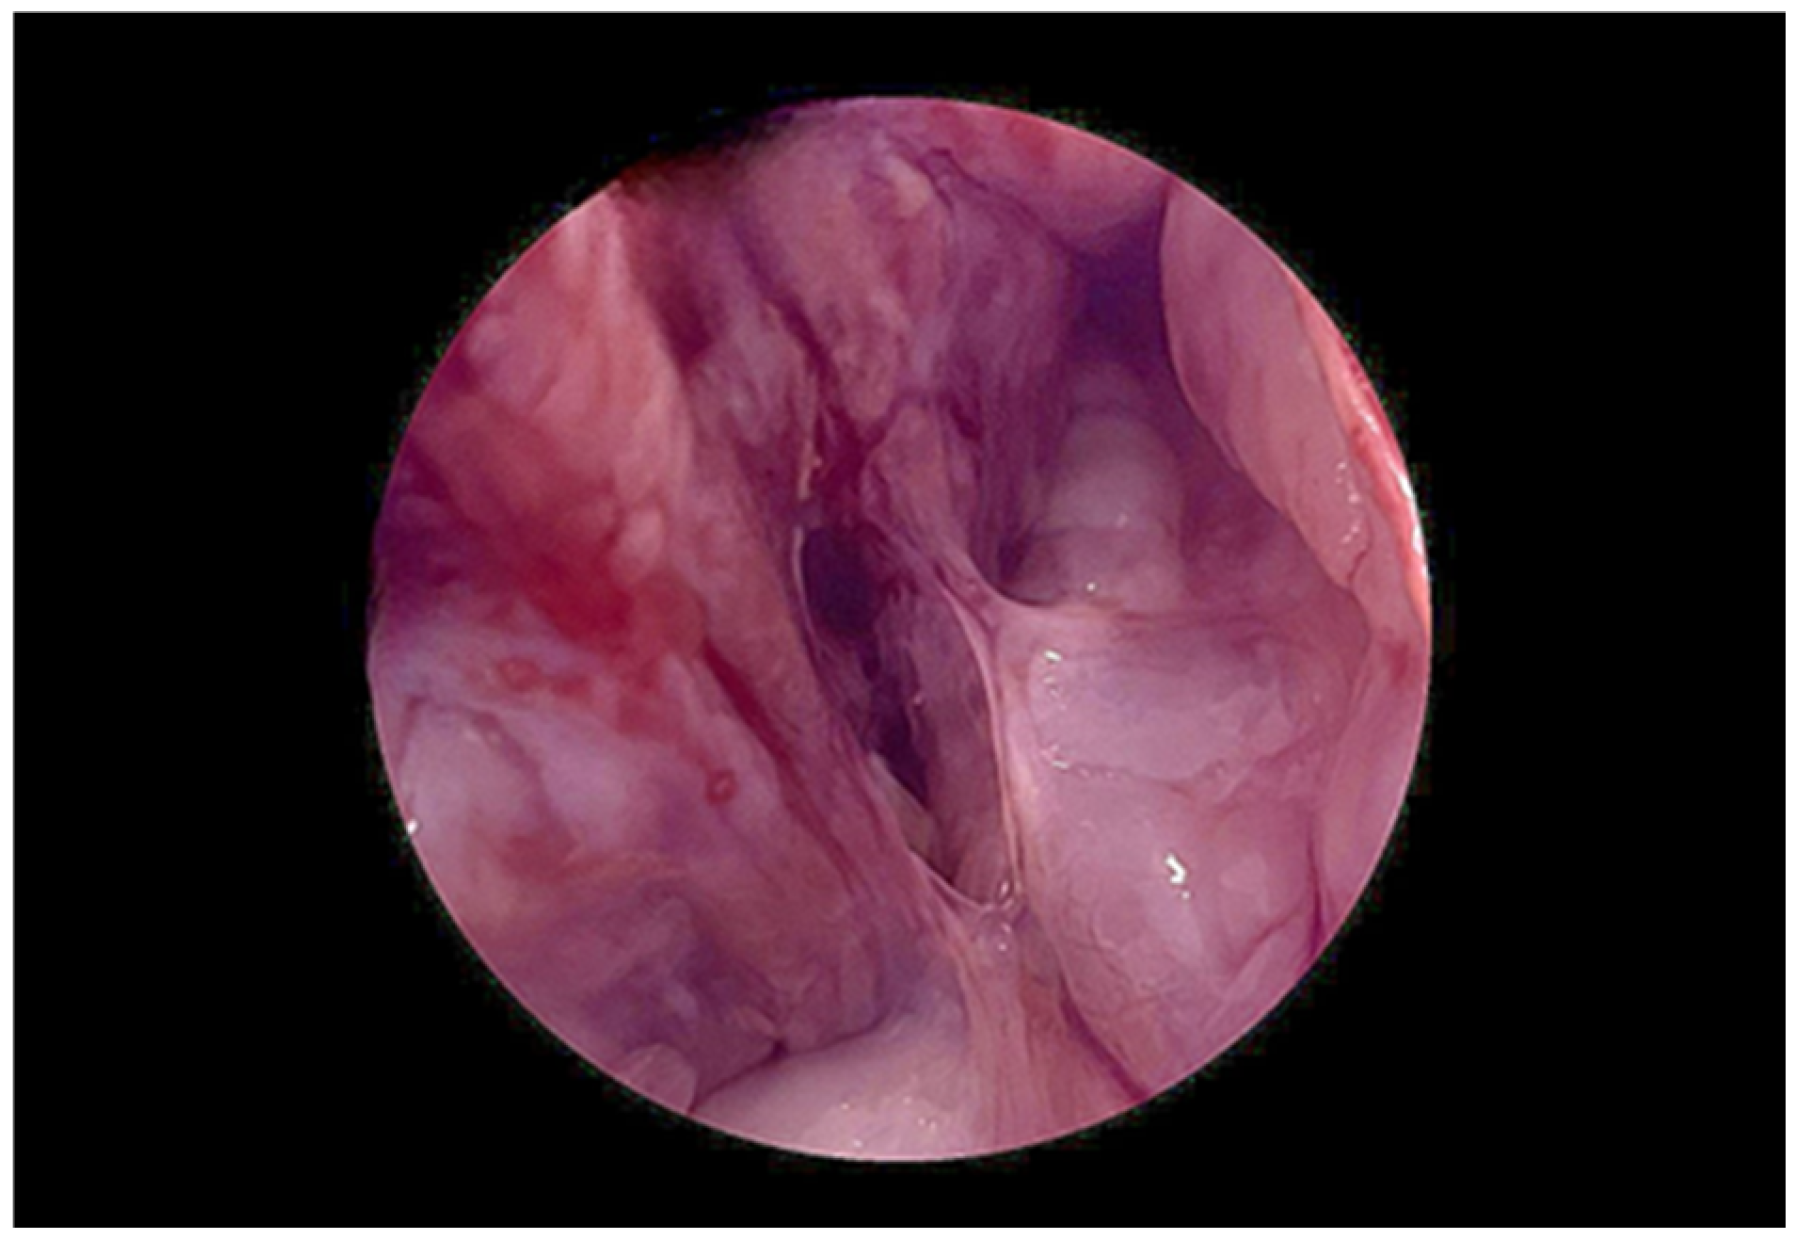

2. Case Presentation